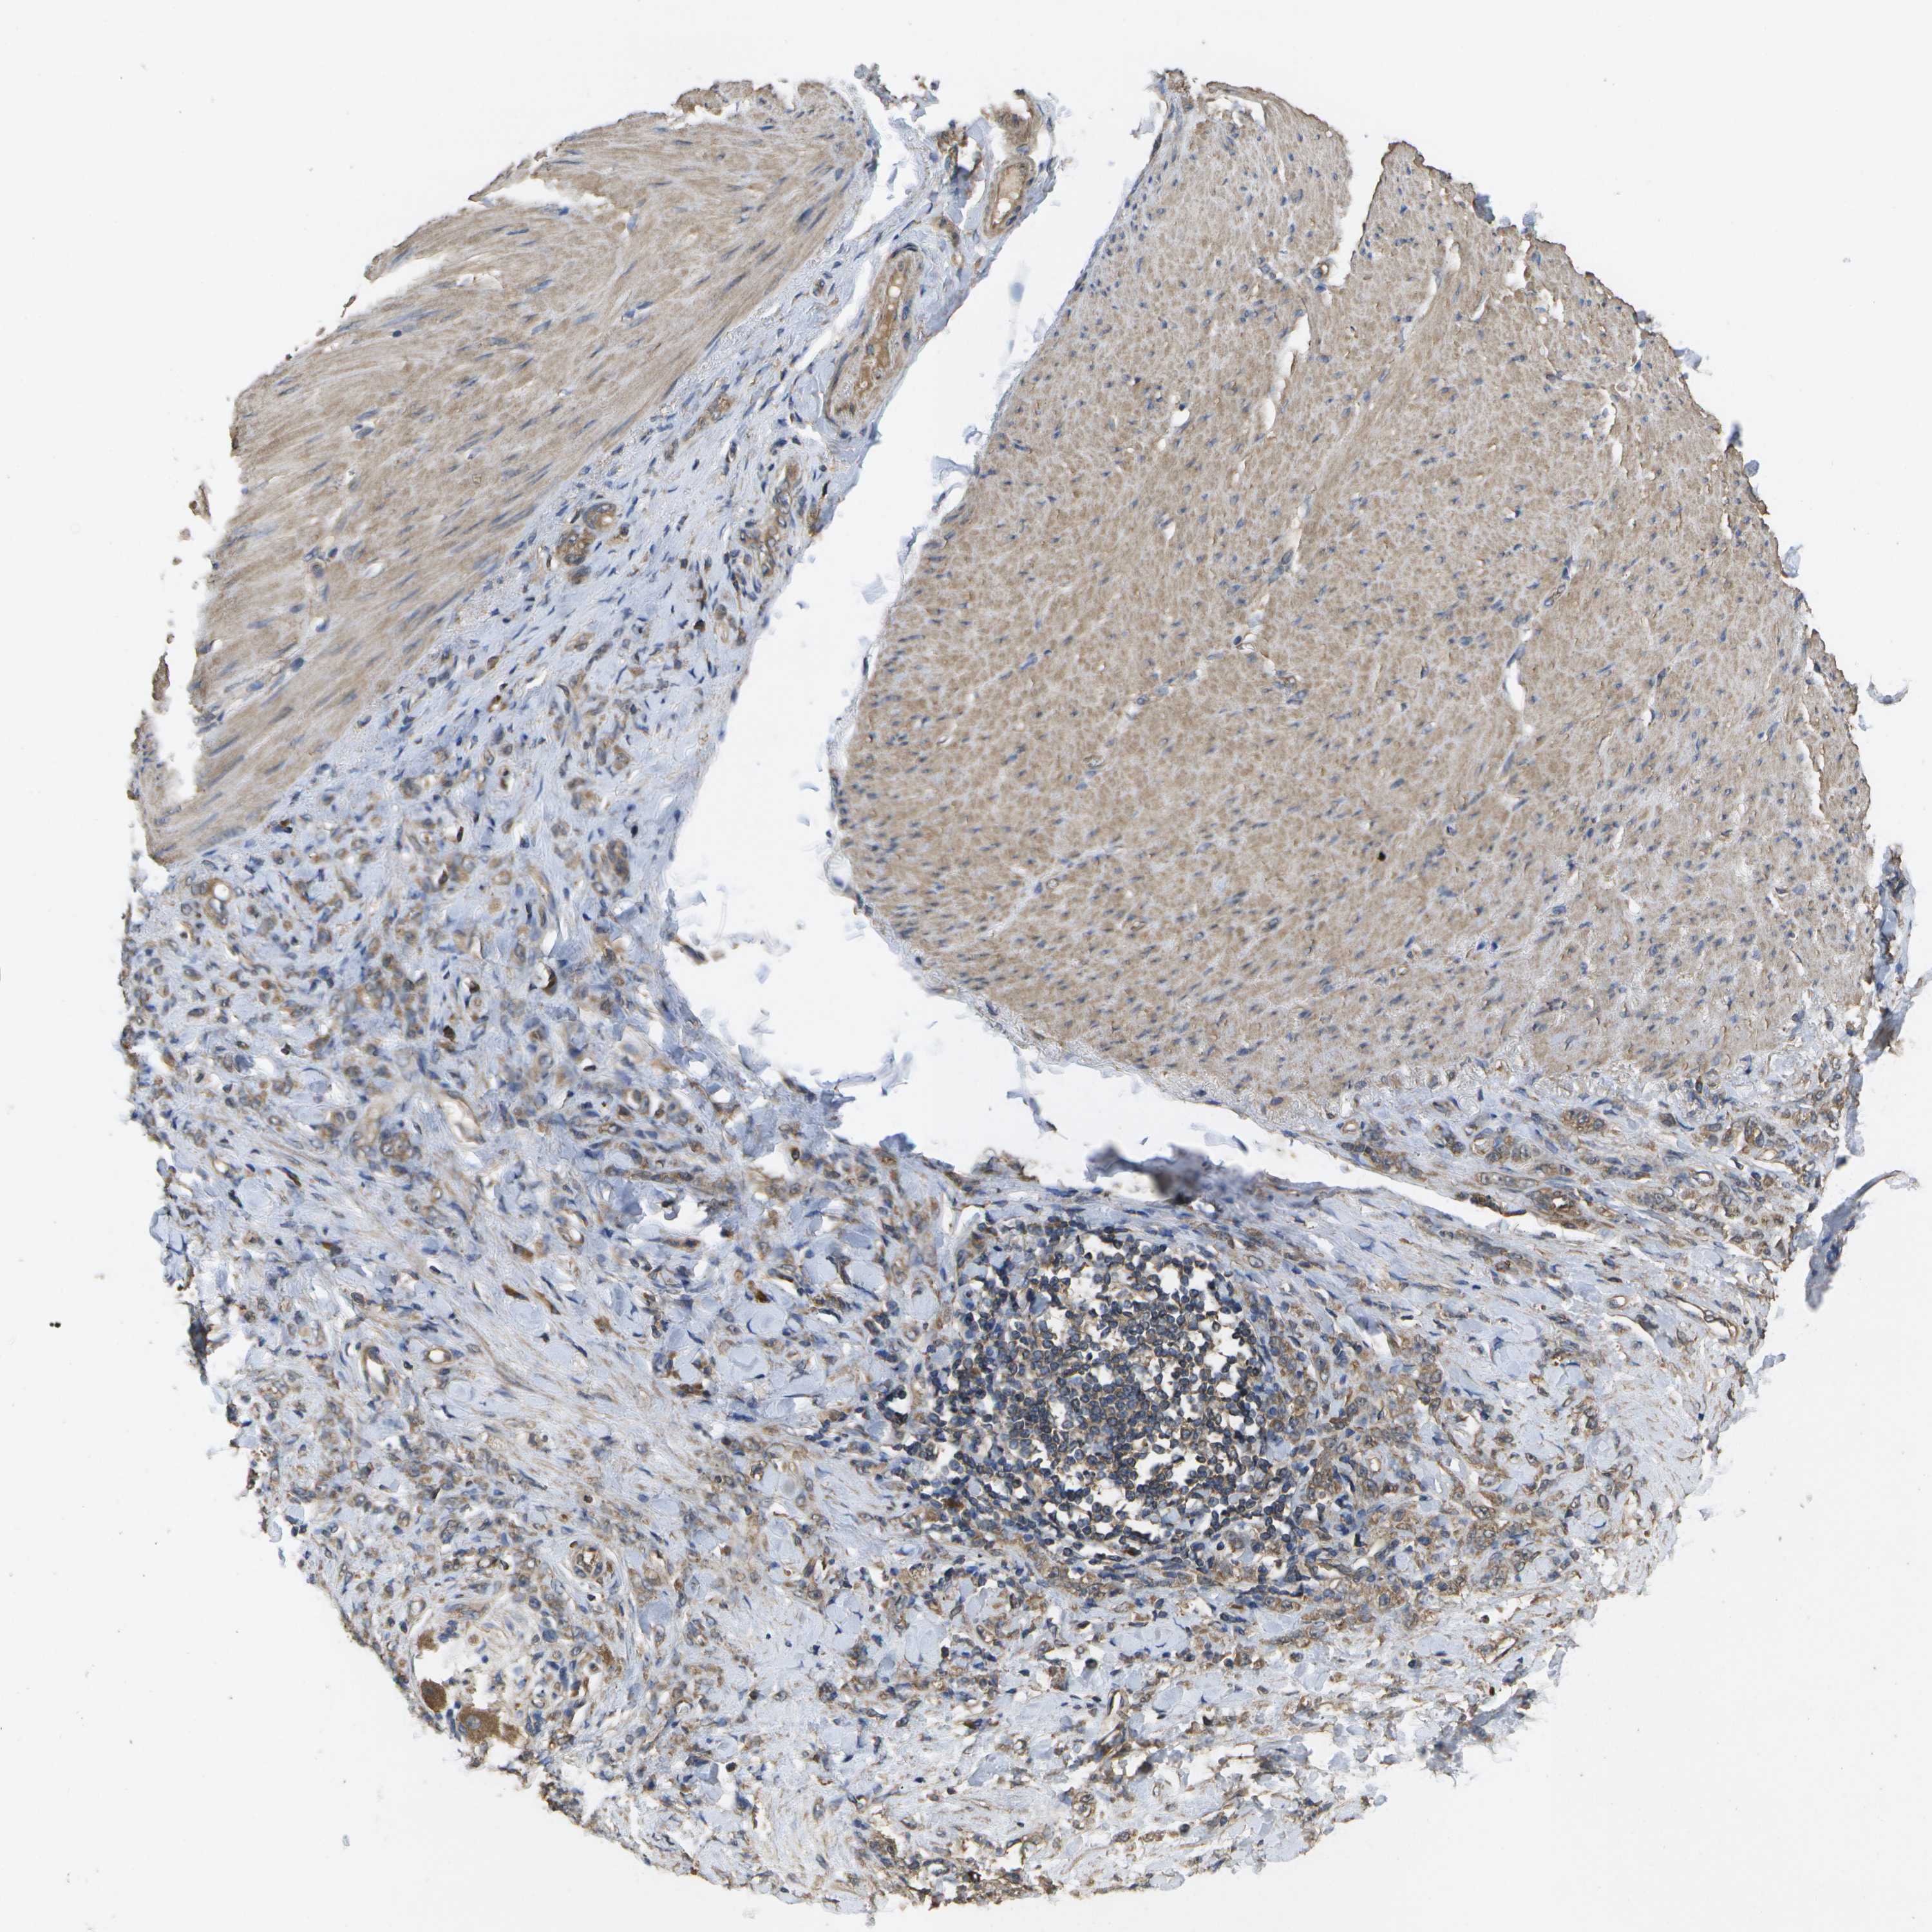

STOMACH CANCER - Protein expressioni

A mouse-over function shows sample information and annotation data. Click on an image to view it in a full screen mode. Samples can be filtered based on level of antibody staining by selecting one or several of the following categories: high, medium, low and not detected. The assay and annotation is described here.

Antibody stainingi

Antibody staining in the annotated cell types in the current human tissue is reported as not detected, low, medium, or high, based on conventional immunohistochemistry profiling in selected tissues. This score is based on the combination of the staining intensity and fraction of stained cells.

Each image is clickable and will lead to virtual microscopy that enables deeper exploration of all samples and also displays staining intensity scores, fraction scores and subcellular localization as well as patient and tissue information for each sample.

Antibody CAB017714

Staining

High

Medium

Low

Not detected

Intensity

Strong

Moderate

Weak

Negative

Quantity

>75%

75%-25%

<25%

None

Location

Nuclear

Cytoplasmic/membranous

Cytoplasmic/membranous,nuclear

Adenocarcinoma, NOS

Adenocarcinoma, High grade